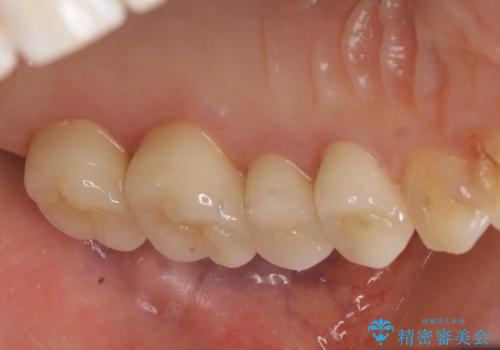

- 左上の奥歯を綺麗にしたいといらっしゃった方の症例です。

左上4、5、6、7番目の歯をオールセラミッククラウンにより補綴しました。

今回用いたオールセラミッククラウンは、ジルコニアフレームという白い素材の上にセラミックを盛っているため審美性が非常に高いのが特徴です。

またジルコニアは人工ダイヤモンドの材料にも使われているほど高い強度を持っており、そのためオールセラミッククラウンは審美性だけでなく、奥歯やブリッジの補綴も可能とするクラウンです。